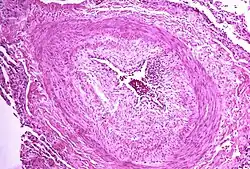

Micrograph showing arteries in pulmonary hypertensive with marked thickening of the walls

The pathogenesis of pulmonary arterial hypertension (WHO Group I) involves the narrowing of blood vessels connected to and within the lungs. This makes it harder for the heart to pump blood through the lungs, as it is much harder to make water flow through a narrow pipe as opposed to a wide one. Over time, the affected blood vessels become stiffer and thicker, in a process known as fibrosis. The mechanisms involved in this narrowing process include vasoconstriction, thrombosis, and vascular remodeling (excessive cellular proliferation, fibrosis, and reduced apoptosis/programmed cell death in the vessel walls, caused by inflammation, disordered metabolism and dysregulation of certain growth factors).[27][28] This further increases the blood pressure within the lungs and impairs their blood flow. In common with other types of pulmonary hypertension, these changes result in an increased workload for the right side of the heart.[16][29] The right ventricle is normally part of a low pressure system, with systolic ventricular pressures that are lower than those that the left ventricle normally encounters. As such, the right ventricle cannot cope as well with higher pressures, and although right ventricular adaptations (hypertrophy and increased contractility of the heart muscle) initially help to preserve stroke volume, ultimately these compensatory mechanisms are insufficient; the right ventricular muscle cannot get enough oxygen to meet its needs and right heart failure follows.[16][28][29] As the blood flowing through the lungs decreases, the left side of the heart receives less blood. This blood may also carry less oxygen than normal. Therefore, it becomes harder and harder for the left side of the heart to supply sufficient oxygen to the rest of the body, especially during physical activity.[30][31][11] During the end-systolic volume phase of the cardiac cycle, the Gaussian curvature and the mean curvature of the right ventricular endocardial wall of PH patients were found to be significantly different as compared to controls.[32]